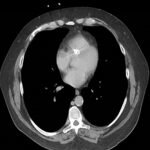

Endovascular coil embolization continues to become a more frequent modality of addressing hemorrhage and bleeding in patients. Migration refers to the coil unraveling or moving from the original embolization site. Migration of a coil is a known complication which can lead to serious consequences based on where the coil migrates. Despite increasing efforts to improve safety and technique, the risk of migration remains. We present a case of an embolization coil that migrated to the right ventricle, which was incidentally found roughly 2 months after undergoing an interventional radiology procedure for gastric variceal bleeding. The patient presented to the emergency department with dyspnea and abdominal pain. Unique images were obtained during his visit and in subsequent follow-up. As use of vascular embolization coils continues to become more commonplace, understanding the risks and complications of these procedures remains an important aspect of providing care for patients once they have left the interventional radiology suite. Coil migration should be a differential to consider in patients who present to the emergency department with signs or symptoms of arrhythmia or pulmonary embolism who have undergone a coil embolization procedure.